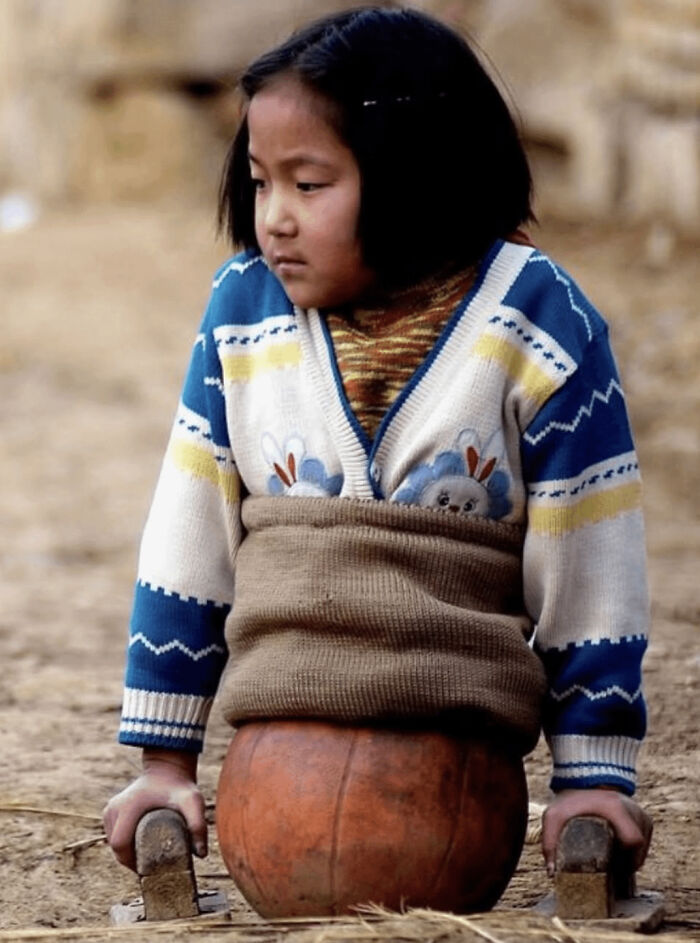

Basketball Girl

After losing both legs in a car accident at age 4, she had no access to prosthetics in her rural village in Yunnan, China. Her family improvised, cutting a basketball in half to help her move around.

By age 10, Qian had learned to walk using her hands and the basketball for balance. Locals nicknamed her “Basketball Girl.” Her story gained national attention in 2005, leading to free medical care and prosthetic limbs from the China Rehabilitation Research Center.

She later received larger limbs as she grew. But by age 11, her treatment ended—and she could no longer attend school due to financial hardship.

Qian’s story highlights global disparities in healthcare access, and the extraordinary will to survive.

This is so terribly sad and unfair, makes me feel sad. I just googled her and am pleased to read that now she has prosthetic legs.